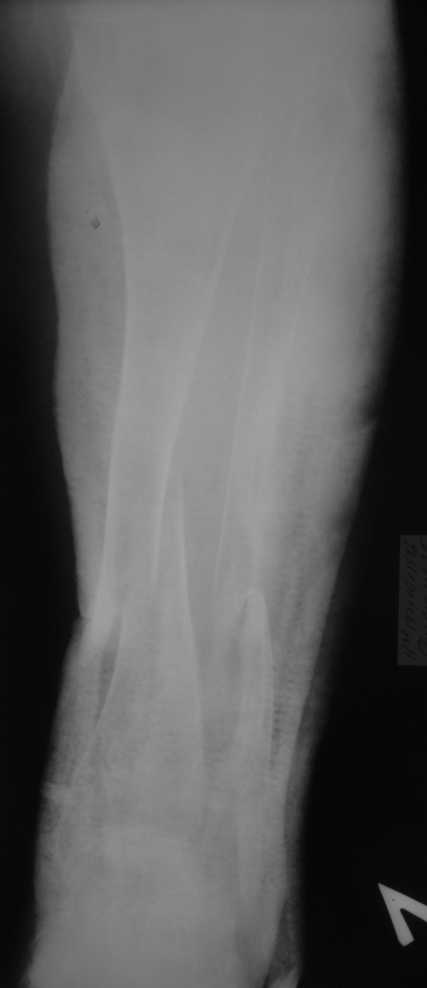

Но даже при малоинвазивной методике лечения применимой для даной больной существуют следующие проблемы: выраженный остеопороз, тонкий кортикал, очень широкий канал.

Контрольные рентгенограммы прилагаю.

Проблема в том, что в сагитальной плоскости угол голеней =30 градусам. Ширина канала 30.